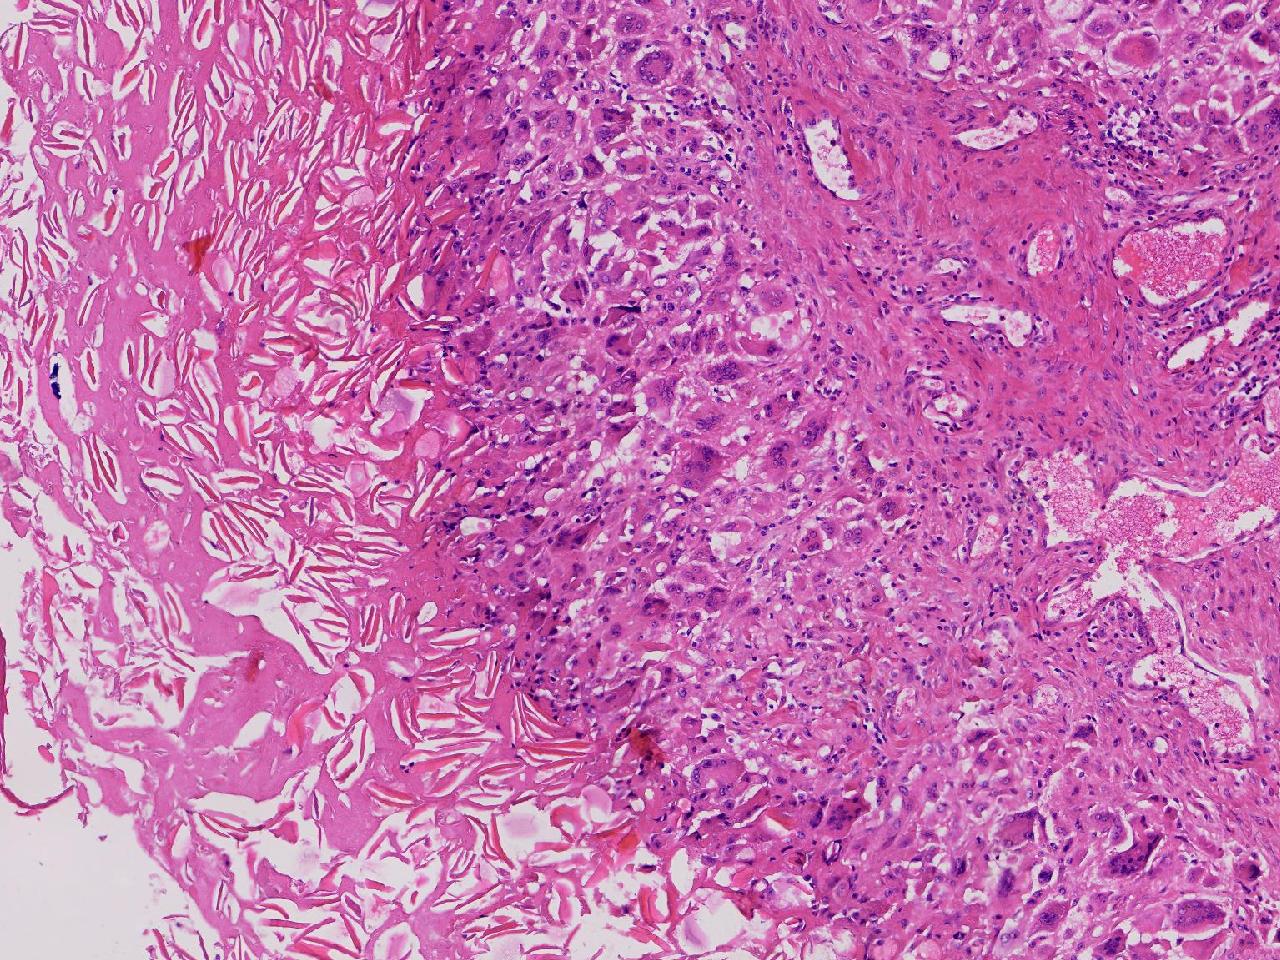

皮样/表皮样囊肿伴周边异物巨细胞反应?

右侧臀部皮下肿物10余年,渐增大,无破溃,无疼痛。

右侧臀部皮下肿物

囊性肿物一个,直径2.5厘米,肿物位于皮下。

异物肉芽肿性炎?

表皮样囊肿伴异物肉芽肿性炎。